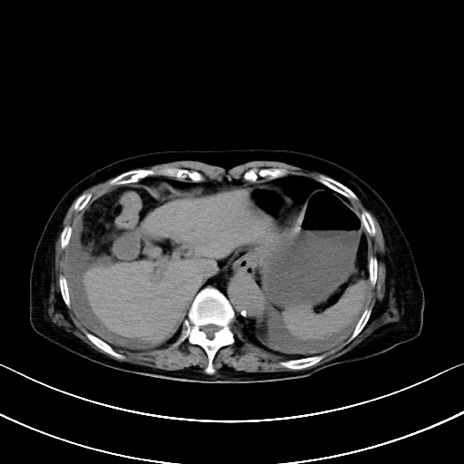

症例40(横断像)他院1日前

横断像